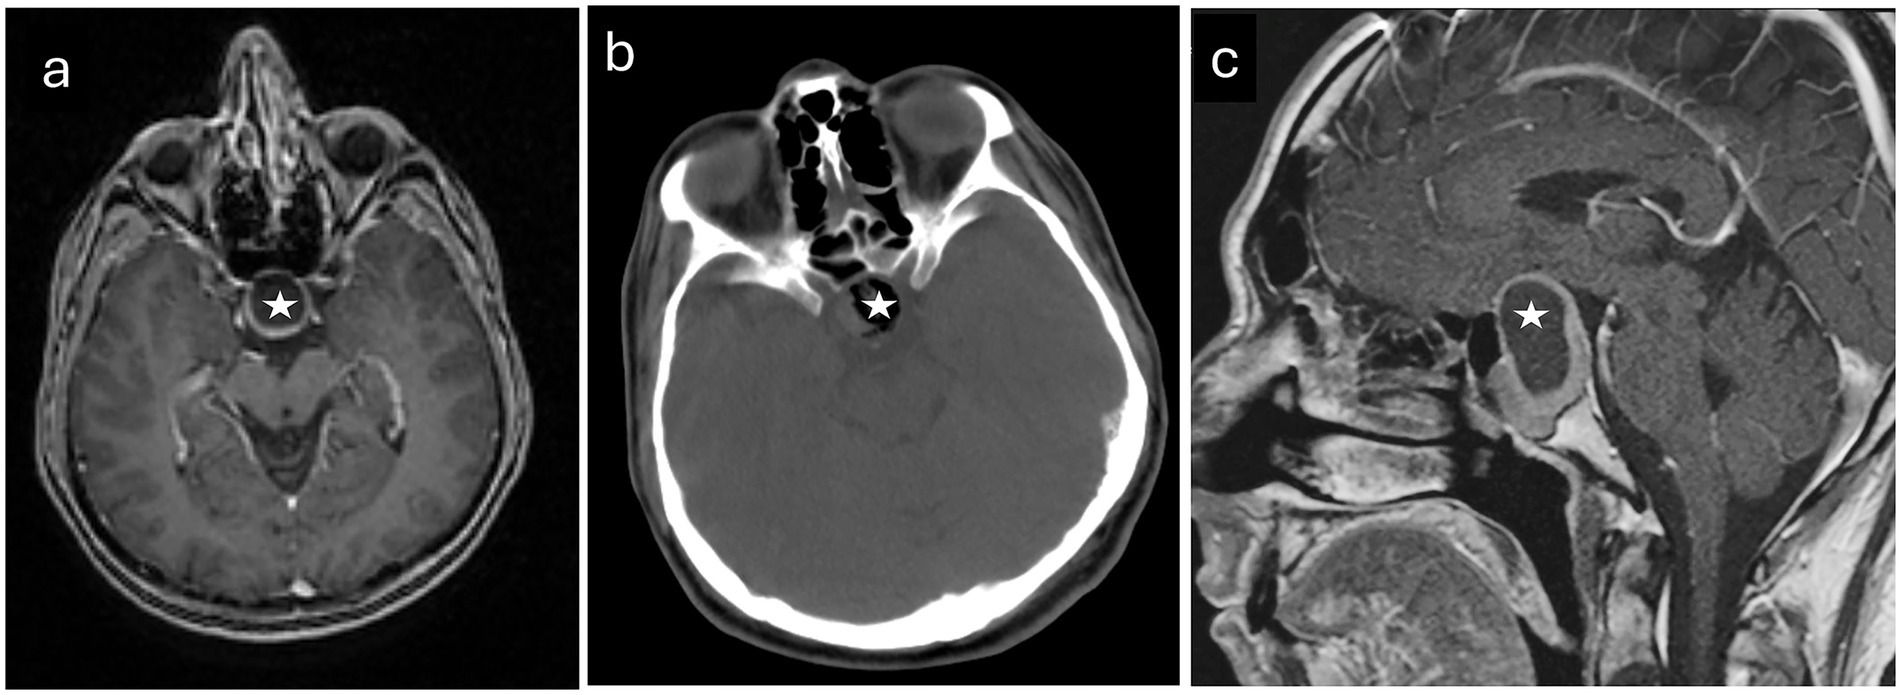

All MRI data was processed in a virtual environment. A sample radiological image included in the study is shown in Figure 1. To detect volumetric differences, MRIs of 86 control subjects without CNS disorders and 90 patients with PitNET were obtained through archival scanning. MRI data were converted to DICOM using Radiant-DICOM-Viewer software.1 Image files in sagittal 3DT1 DICOM (Digital Imaging and Communications in Medicine) format for all participants were converted to NIFTI-1 (Neuroimaging Informatics Technology Initiative) format and uploaded to the vol2Brain system.

Figure 1. Radiological images pertaining to a representative patient diagnosed with pituitary neuroendocrine tumor who participated in the study. (a) An axial T1-weighted magnetic resonance image acquired prior to surgical intervention. (b) A computed tomography scan obtained before the operation. (c) A sagittal MR image taken preoperatively. The tumors are identified by white stars.